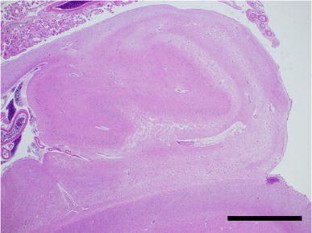

Hippocampal sclerosis is defined as selective neuronal loss and gliosis of the hippocampus with heterogeneous etiologies, including neurodegenerative tauopathies. We report a 78-year-old woman who presented with depression, in whom postmortem examination revealed almost complete loss of neurons with gliosis in the subiculum and CA1-3 regions of the hippocampus and abundant neuronal cytoplasmic inclusions in the dentate gyrus. The inclusions were round, slightly basophilic and argyrophilic, resembling Pick bodies. However, they were Gallyas- and 4-repeat tau-positive, and 3-repeat tau- and ubiquitin-negative. To our knowledge, the histopathological features in this case were different from those in hippocampal sclerosis or 4-repeat tauopathies reported previously. It is likely that this case is a new variant of 4-repeat tauopathy presenting with hippocampal sclerosis.

Fig. 1